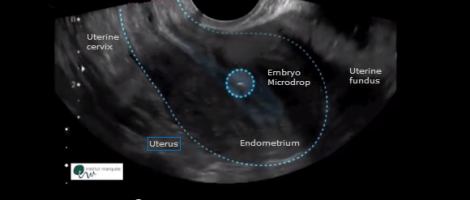

In the first images, we can observe how the microdrop with the embryos passes through the catheter and it is smoothly deposited 1, 2 or 3 cm away from the fundus of the uterus.

In the following ultrasounds the microdrop moves through the endometrial cavity with different undulating, vibratory, slow, fast movements and with resting stages.

In all cases, it is confirmed how the embryos have changed its position with regard to the distance from the uterine fundus after one hour, where it was initially deposited, regardless whether it was 1, 2 or 3 cm away or not.